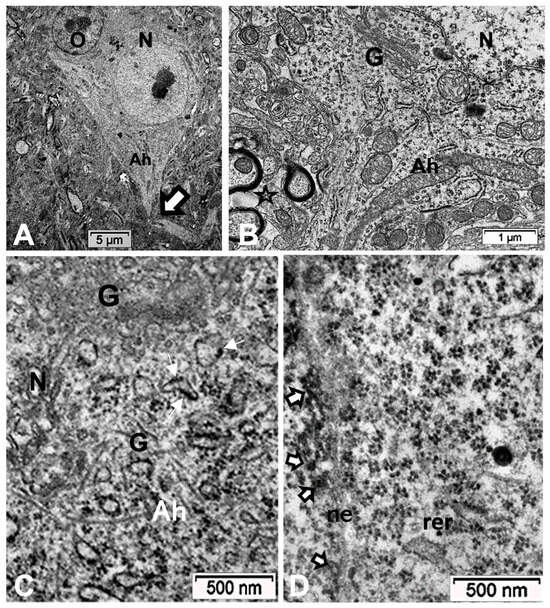

2.3. The ARL13B Immunolabels in the Axon Hillock to Extend in the Axon Initial Segments

Other cell types, including those of the neuroglial types and capillary endothelial cells, can be found among the light brownish hue background. Figure 3, Figure 4, and Figure 6A also convinced us about the ARL13B labeled structure when, as shown in Figure 6B,C, toluidine blue stain allowed us to show similar cell extensions of ODS thalamic nerve cell bodies in epoxy 1-µm thick sections, where short but chubby axon hillocks extending into AIS were strongly stained. It is only through using TEM views that equivalent structures were identified and deciphered with ultrastructure, such as those illustrated in Figure 7A–C. In the meantime, both closest to the damaged edge of the chronic hyponatremia demyelinated zone, as shown in Figure 3 and Figure 4, HN and ODS12h as shown in Figure 6A–C, other immunolabeled cone-shaped appendages appeared to issue from the neuroplasm whose outline offered the same intense brown contrast found in Figure 6A. In Figure 6A, the hemalum stained the nucleolus in a blue and purplish hue and the epoxy equivalent structure toluidine blue-stained sections revealed an intense basophilia almost as if each heavy spike issued from the perikarya, close to the nucleus (Figure 6B,C). These features altogether confirm that both LM staining patterns have marked and recognized enriched parts of the axon hillock that formed and extended into AIS. In addition, they were repleted with both freed, polyribosomal and attached endoplasm ribonucleoproteins amongst few mitochondria, but still leaving enough intracellular neuroplasm to gain an overall toluidine blue orthochromaticity (Figure 7A–C). Again, with a fine structure, those ODS12h and ODS48h thalamic nerve cell body features revealed nucleoli components that comprised abundant transcriptions and translations. The same ODS12h thalamic nerve cell bodies contained vestiges of physiological stress that showed as fine injuries that altered the neuroplasm contrast, facing all the nuclear pores, and some endoplasmic reticulum cisterns or parts were seen as if the scratches of nails were left among them (Figure 7B).

3.2. The Translational Aspects of the Emergence of a Primary Cilium among Neurons Outside the ODS Epicenter

The LM yellow–ochre hue aspects of the ARL13B immunolabeled thalamic tissues appear as if covered with an overall from which scattered hole-like, oval to round shapes appear as ‘holes in the fabric’, where the nerve cell bodies, either isolated or as joined pairs or triplets exhibit poor contrast, as shown before with resilient nerve cells [66]; meanwhile, they maintain low resistance contact junctions with each other, as noted in Figure 12A [69]. However, the nuclei, poorly stained, disclose orthochromasy where contrasted nucleoli in pale blue staining according to hemalum reveal accumulated RNA transcripts with a chromatin DNA-stained dark blue hue [155,156]. Similarly, the semi-thin epoxy sections, prepared to choose zones to be ultra-cut, stained by toluidine blue, allow us to verify the abundant transcripts located in an appendix-like zonation with profused ribonucleoproteins [157,158]. Here, the axon hillock extends into the ARL13B labeled segment that is similarly richly endowed by transcripts, detected where the primary cilium and a future AIS grew after ODS, away from the demyelinated ODS epicenter, in the outskirts of the demyelinated thalamic zone. The resilient neurons show a perikaryal zone where most of the cells typical organelles and inclusions are located, including the Nissl bodies, contained cytoskeletal components among sparse polyribonucleoproteins associated or not with the endoplasmic reticulum along with mitochondria and apparently haphazardly oriented neurotubules (also known as microtubules) that are ultimately associated with the changing funnel shape of the cell extension that then possess these neurotubules, associated with neurofilaments and free ribosomes [159]. These neurocytologic components can also be viewed in our resilient neurons illustrated in Figure 7, Figure 8E, Figure 10, Figure 11, and Figure A2 where AIS is forming, as further explained in [159], with the earliest ultrastructural publications. There, according to the ODS lapse of time views, the typical perikaryal neuroplasm showed amassed polyribonucleoproteins (polysomes) within a distal region that yielded a sort of exocyst extended into a comma-shaped and in distal ODS into more or less long cylindrical extensions marked by an ARL13B label. It is after scrutiny of the ultrathin sections of these resilient neurons that a few of these sections (1 out of 15) revealed a display of a primary cilium (Figure 10A,B). These unique observations among ODS CNS damages confirmed those ARL13B labelings, similarly to those revealed for some oligodendrocytes within the same murine ODS damage region [68]. The occurrence of such neuronal primary cilium outgrowth was not investigated elsewhere in the CNS; one of the reasons is that, unlike the thalamic nuclei, the centropontine regions or subcortical regions are inconsistently affected by demyelinating lesions in the model of ODS in mice [62].